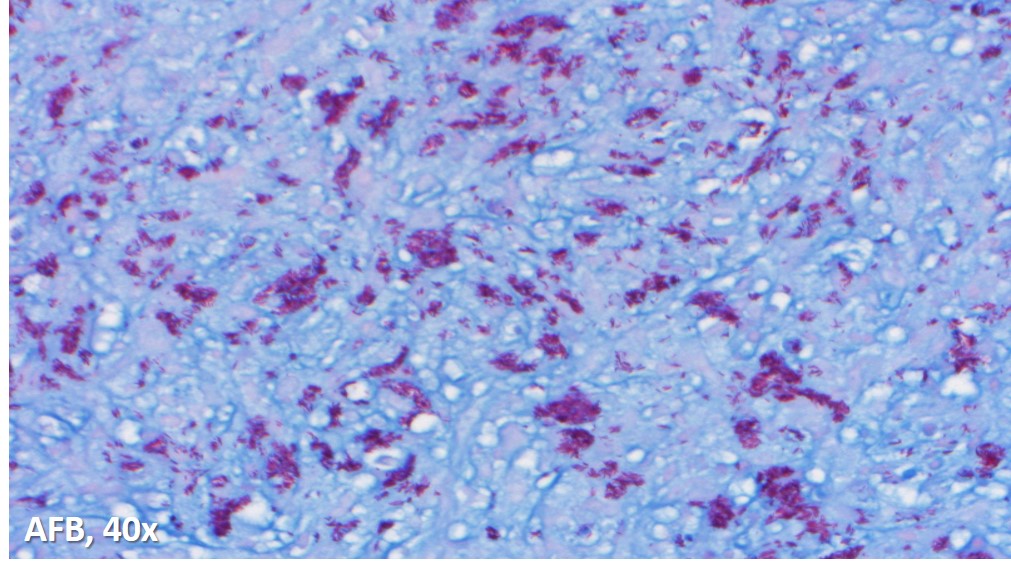

Immunoperoxidase and special stains were performed on this case. The cells were diffusely positive for CD45 and CD163, and negative for keratin cocktain, S100, CD1a and CD30. AFB and Fite were positive for acid fast bacilli, and highlighted abundant organisms. The findings were consistent with an infectious lymphadenitis, and most suggestive of a nontuberculous mycobacterial infection.